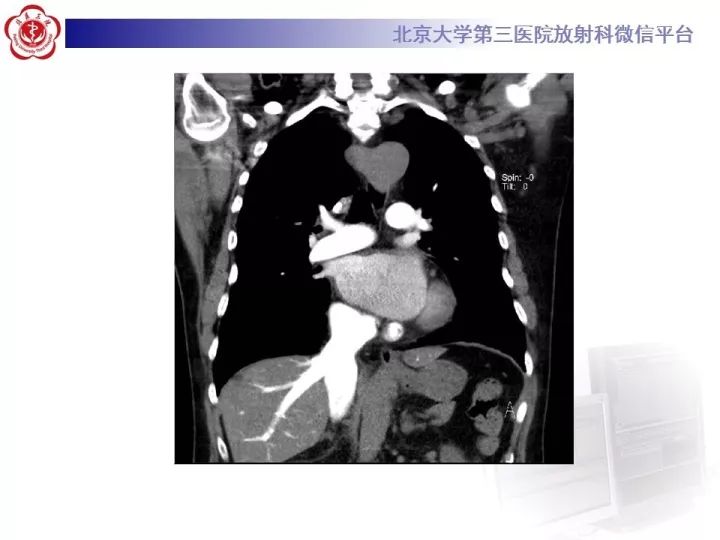

【病例】双主动脉弓畸形1例CT